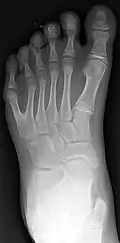

Diagnosis

Classification is performed by using x-ray imaging to see the bone structures.[19]